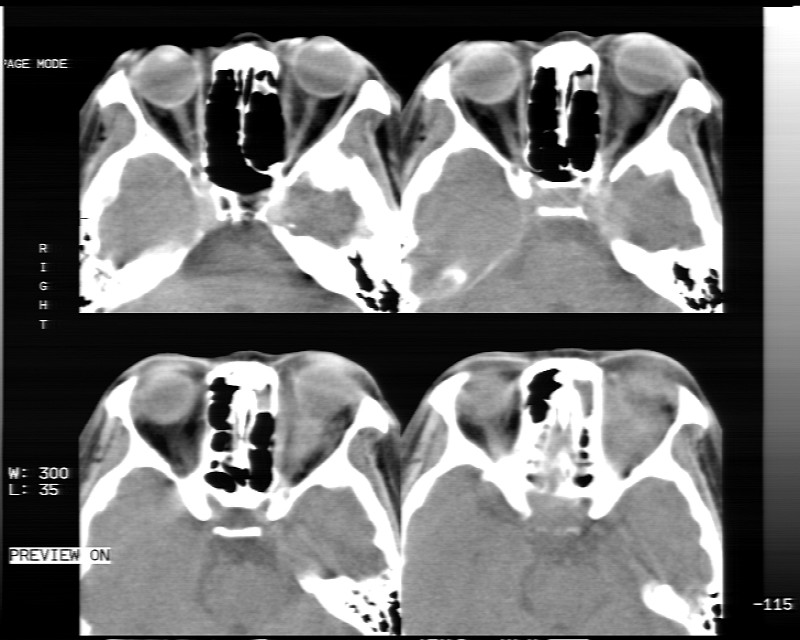

女性,40岁,左眼疼痛,视力模糊,五年曾行左眼脂肪瘤手术。

患者现病史不知持续有多久了,现片示眶内病灶边缘较模糊,眶脂混浊,多考虑炎性假瘤,不除外肿瘤

1)左眼眶内占位性病变,性质待定(不排除炎性假瘤);建议行进一步检查。2)左侧额窦炎。